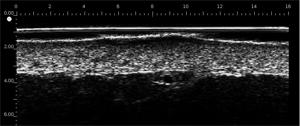

DERMCUP permite la adquisición no invasiva de secciones verticales de la piel in vivo

25 MHz: 16 mm x 12 mm

La dermis es ecogénica. Los ecos provienen de la red de fibras de colágeno y fibras elásticas. En relación a la dermis, las lesiones (tumores, quistes, angiomas …) aparecen como áreas hipoecoicas.

Gracias a su frecuencia de 25 MHz y 50 MHz , el DERMCUP ofrece una alta resolución:

Axial: 30 μm

Lateral: 120 μm

En dermatología, es necesario visualizar lesiones infra-centimétricas. Esto no se puede hacer con los escáneres de ultrasonido tradicionales equipados con sondas de 7-13 MHz.

El DERMCUP es adecuado para ver lesiones del tamaño de la décima de milímetro.